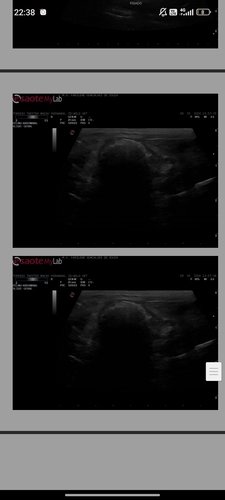

Eu sou a Nanda, e criei essa vaquinha com o intuito de ajudar meu ratinho Twister chamado torresmo pra retirada de dois tumores. Eu recebi a notícia em que torresmo tinha um tumor localizado dentro do intestino, no meio de 2024, porem como é um lugar muito sensível, uma cirurgia perigosa, não conseguimos fazer biopsia nem a retirada dele, apenas tratar com remédios pra dor e remédios para inibir o crescimento do tumor. Agora em 2025, o torresmo está com outro tumor, que está crescendo muito rápido e não sabemos qual a causa dele, nem se ele é benigno ou maligno, por isso eu em conjunto com o veterinário que o acompanha faz tempo decidimos fazer a cirurgia de retirada dos dois tumores, mesmo que arriscado, é muito pior o tumor ficar crescendo e crescendo e poder acabar com a vida do meu ratinho.